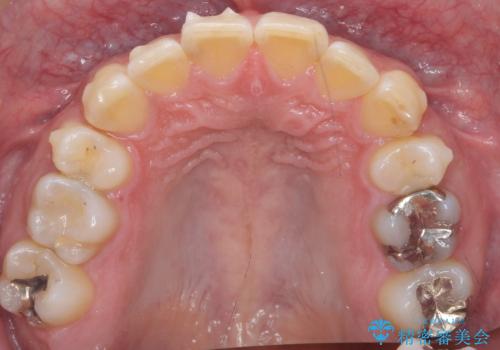

- 前歯だけ歯並びを治したいとのご希望で来院された患者様です。

数年前にワイヤー矯正を行ったものの、少し後戻りしてしまったそうです。

上の前歯が斜めに見えること、犬歯と小臼歯の間の隙間、上下顎前歯のがたつきを治すことをご希望されていました。

気になるのは前歯だけで、奥歯の咬み合わせは気にならないとのことでした。

ご予算と患者様のご希望により、インビザライン・ライト(マウスピース14枚)によるマウスピース矯正を行いました。